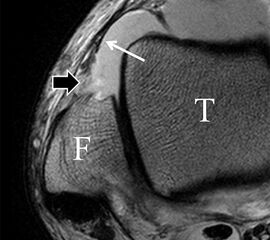

Der Ursprung des Ligamentum fibulocalcaneare liegt unmittelbar kaudal und dorsal des Ursprungs des Ligamentum fibulotalare anterius, so dass gehäuft kombinierte Verletzungen und auch ein gemeinsamer knöcherner Ausriss beobachtet werden. Nach kaudal dorsal verläuft das Band dann nach medial konvex unter die Peroneussehnen. Danach ist ein schräg deszendierender, gestreckter Verlauf bis zum calcanearen Ansatz abgrenzbar (Abb. 10). Dieser zu allen drei Standardebenen schräge Verlauf erschwert häufig die Diagnostik des LFC vor allem bei subtileren Verletzungen. Spezialprojektionen, die dem Bandverlauf orthograd folgen (entweder schräg coronar oder schräg sagittal) erleichtern auch hier die Diagnostik (Abb. 11) insbesondere nicht dislozierter Avulsionen. Assoziierte Verletzungen der Peroneussehnenloge müssen mit beurteilt werden, wobei neben Verletzungen der Sehnen und Sehnenscheiden die Beurteilung des Retinaculum peroneum superius und inferius wichtig ist. In einem Kollektiv von Patienten mit chronischen Außenbandinstabilitäten weisen 50% der Patienten eine Verletzung dieser Strukturen auf 5. Auch hier erleichtern hochauflösende Techniken die Diagnostik (Abb. 12).